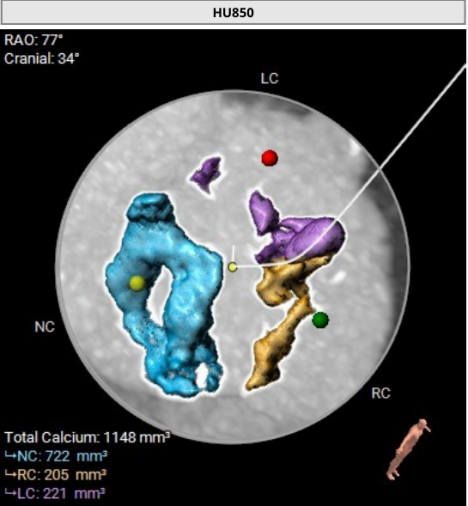

术前CT评估: 主动脉根部评估,Type1型(L-R)二叶式主动脉瓣(瓣口周长76.1mm,平均径24.2mm),瓣叶增厚,重度钙化(HU850:1148mm³)。